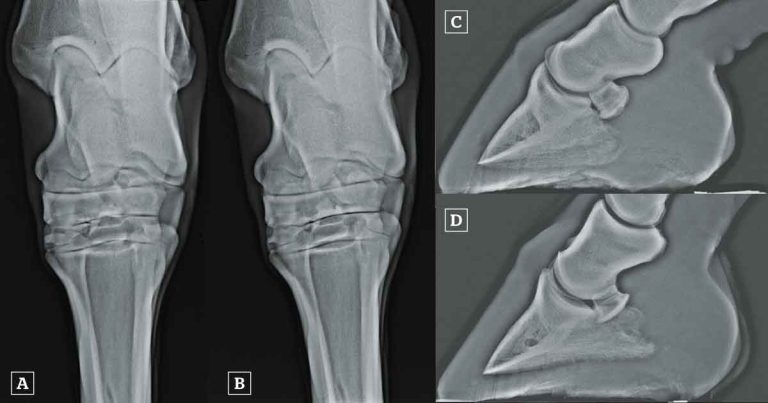

Figure 3. [A] Dorsoplantar radiograph of a hock acquired with a horizontal beam. The centrodistal and tarsometatarsal joint spaces are poorly defined (arrows). Artefactual narrowing of the distal tarsal joints is common in dorsoplantar images acquired with a horizontal beam because the distal tarsal joints slope from proximal, dorsally to distal, plantarly. [B] Dorsoplantar radiograph of the same hock as in A, acquired with a beam angled 5° distally (dorsal 5° proximal-plantarodistal oblique). The centrodistal and tarsometatarsal joint spaces are clearly visible and no narrowing exists. [C] Lateromedial radiograph of a foot of non-diagnostic quality. This is not a true lateromedial because the distal condyles of the middle phalanx and the palmar processes of the distal phalanx are not superimposed. The demarcation between the palmar compact bone of the navicular bone and the spongiosa, and the integrity of the palmar compact bone, cannot be assessed, because the beam is not perpendicular to the long axis of the navicular bone. The navicular bone cannot be evaluated using this image. [D] Lateromedial radiograph of the same foot as in C, acquired with better positioning of the foot. This image is of good diagnostic quality. The palmar compact bone of the navicular bone is well demarcated because the beam is perpendicular to the long axis of the navicular bone. There is mild proximal and distal extension of the palmar compact bone of the navicular bone.

In addition to the selection of appropriate exposure factors, appropriate beam centring and collimation, and patient preparation and positioning can vastly alter image quality (Figure 3). Each image should be critically appraised for diagnostic quality, and repeated if necessary.